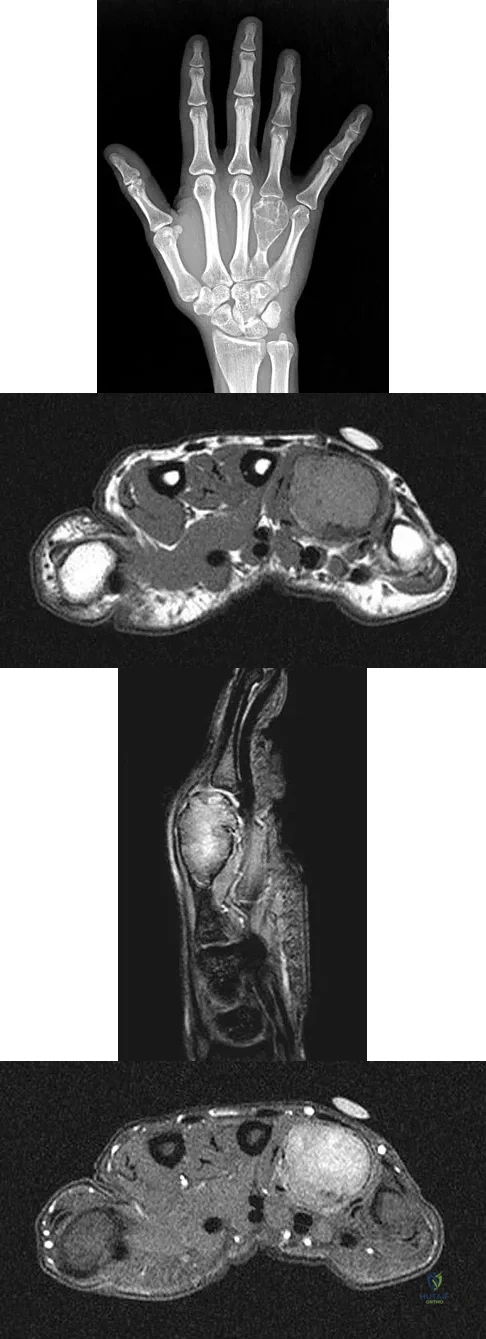

A 26-year-old man has had hand pain and progressive swelling in the knuckle for the past several months. He denies any trauma to the hand. The ring finger metacarpophalangeal joint is tender, and there is loss of motion in the digit. Figure 32a shows the radiograph and Figures 32b through 32d show the T1-weighted, T2-weighted, and gadolinium MRI scans, respectively. What is the most likely diagnosis?

Explanation